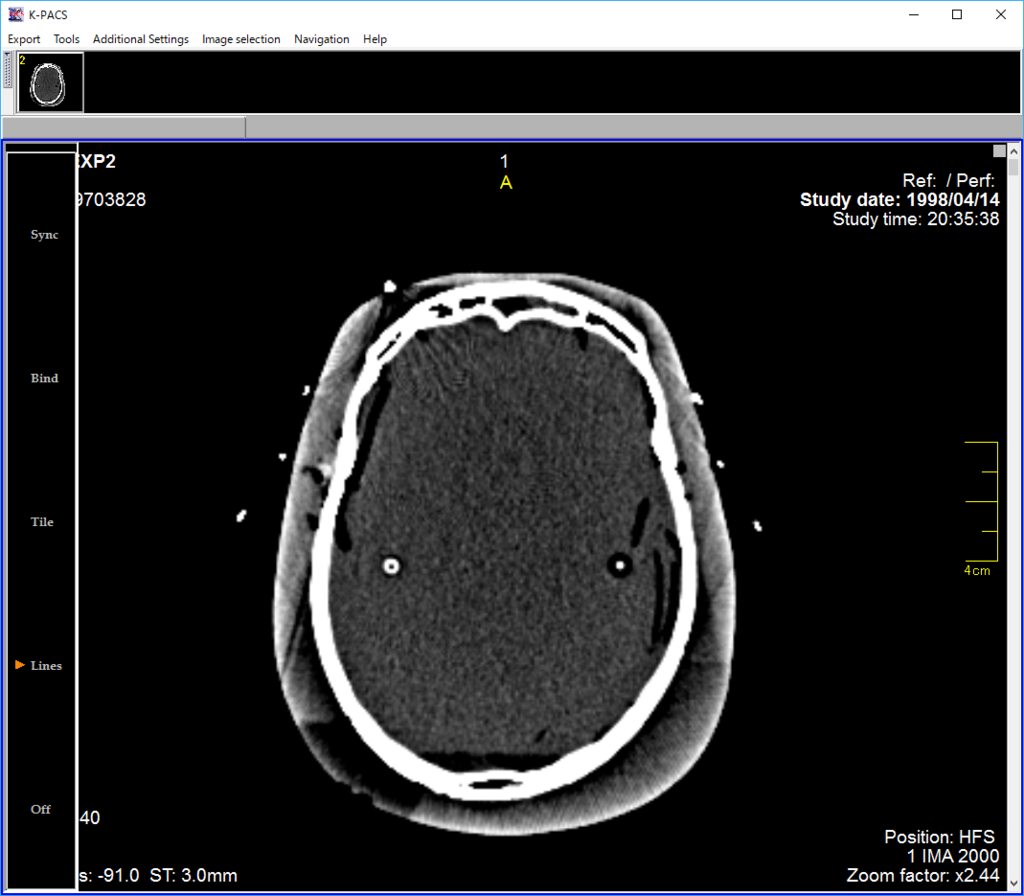

DICOMserver構築②~Conquest・postgreSQL on Ubuntu16.04

以前DockerImageを使って、簡単なDICOMserver構築をブログにアップしましたが、今回は一つ一つコマンド入力しながらインストールして、データベースもPostgreSQLに変更してみます。

今回も仮想マシン(Ubuntu64bit 16.04LTS)上にサーバー構築します。

次にクライアントのKPACSに接続するための設定です。

これでKPACSとConquestが接続されているはずです。

DockerでDICOMserver構築①~Conquest、SQLite

フリーのDICOM画像serverでConquestというのがあります。

次にクライアントソフトから接続するための設定をします。

クライアントは定番のKPACS。参考サイトからダウンロードしてください。アカウントの作成とログインが必要です。

今度はホストPC上のクライアントソフト(KPACS:DICOMviewer)の設定です。

右上のDICOMsettingボタンを押して、DICOMconfigurationsで、仮想マシンのIPアドレスを入力し設定保存します。

KPACSのQuery→Networkタブを選択→Conquestにチェック→Search filterのSearchボタンを押してみましょう。テストデータが見えました。

接続成功です。